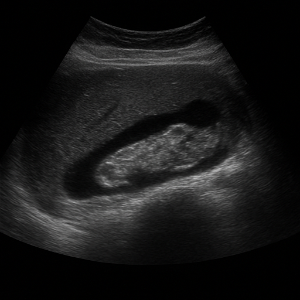

복부초음파는 우리 눈에 보이지 않는 높은 주파수의 소리(초음파)를 배 위에 대고 보내서, 몸속 장기와 혈관 구조를 실시간으로 영상으로 보는 검사입니다. 이 검사는 방사선을 사용하지 않고 통증이나 위험이 거의 없어, 안전하게 여러 번 반복할 수 있어요 .

초음파 기기에는 ‘탐촉자(transducer)’라는 작은 기계가 있는데, 이 기기가 전기 신호로 초음파를 만들어 몸속으로 보내요. 이때 사용하는 주파수는 사람이 들을 수 없는 높은 소리, 보통 2~5MHz 정도예요 .

초음파가 배 안 장기나 조직에 부딪히면 일부는 반사되어 돌아오고, 이 반사파를 탐촉자가 받아 전기 신호로 바꿔요. 컴퓨터가 이 신호를 이용해서 화면에 영상으로 보여줍니다 .

영상이 만들어지는 원리는 시간(반사파가 돌아오는 속도)과 강도(얼마나 세게 반사되었는지)를 컴퓨터가 계산해 이미지의 위치와 밝기를 결정하는 방식이에요. 깊이가 깊을수록 반사되는 시간도 길어지고, 반사파가 세면 화면에서 밝게 나타나요 .